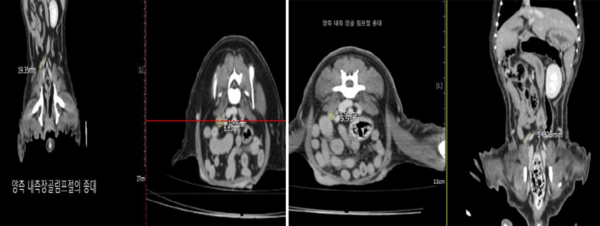

반려견 대상 폴리탁셀 4.5mg/kg 항암효능시험 결과, 림프절 전이암 크기. (좌)투약 전 림프절 전이암 크기(가로 10.06mm-세로 6.63mm-높이 19.35mm), (우)투약 후 림프절 전이암 크기(가로 5.91mm-세로 3.98mm-높이 14.26mm)./현대바이오 제공 반려견 대상 폴리탁셀 4.5mg/kg 항암효능시험 결과, 림프절 전이암 크기. (좌)투약 전 림프절 전이암 크기(가로 10.06mm-세로 6.63mm-높이 19.35mm), (우)투약 후 림프절 전이암 크기(가로 5.91mm-세로 3.98mm-높이 14.26mm)./현대바이오 제공

이번 실험에서는 반려견에게 폴리탁셀의 약물 부작용이 나타나지 않는 최대무독성용량(NOAEL) 이하인 4.5㎎/㎏을 회복기 없이 주 1회씩 3회 연속 투여하고 3주 후에 관찰한 결과, 유선종양 크기가 투약 전보다 무려 76.78% 감소했다. 특히 림프절에 전이된 종양 크기는 투약 전보다 74.01%나 줄어들어 폴리탁셀이 전이암 치료효과도 뛰어남을 입증했다.